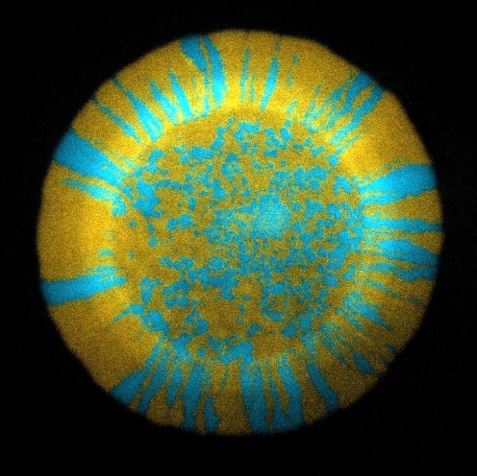

<노란색과 파란색 형광색은 박테리아(대장균)을 나타낸 것으로, AI-2 신호를 생산하거나 제거한다>

유기체 모델인 실험용 쥐를 이용하여, 연구진은 장내의 대장균(Escherichia coli, E. coli)이

AI-2를 생산하고 감지한다는 것을 확인하였다.